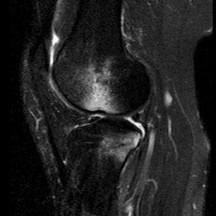

A 45-year-old recreational athlete presents with acute medial knee pain after feeling a 'pop' while deep squatting. MRI demonstrates an extrusion of the medial meniscus of 4 mm and a complete radial tear at the posterior root. Which of the following best describes the primary biomechanical consequence of this specific injury pattern?

A posterior medial meniscus root tear disrupts the circumferential hoop stresses that the intact meniscus relies on to dissipate axial loads. Biomechanical studies demonstrate that a posterior root tear is functionally equivalent to a total meniscectomy in terms of decreasing contact area and dramatically increasing peak tibiofemoral contact pressures, leading to rapid chondrolysis and osteoarthritis if left untreated.